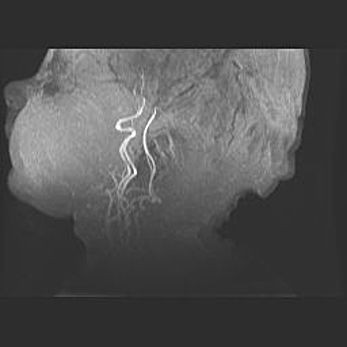

Церебральная ишемия II.

Возраст: 7 дней

Вес: 3350 г

Пол: женский

Окружность головы: 35 см

Срок гестации: 39 недель

Ишемия головного мозга – это состояние, которое развивается в ответ на кислородное голодание вследствие недостаточного мозгового кровообращения. У новорожденных она является следствием дефицита кислорода, что ведет к метаболическим расстройствам различной степени тяжести в тканях головного мозга, в том числе к развитию коагуляционных некрозов и гибели нейронов.